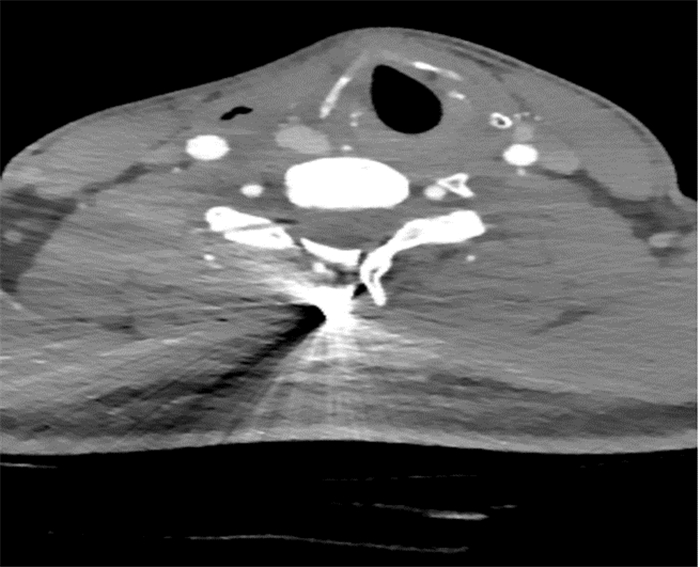

1 辅助检查结果血常规:WBC 8.63×109 L-1, N 0.949, PLT 222×109 L-1,HG 142 g/L。生化:肝功能、肾功能、心肌酶及电解质正常。凝血功能正常。动脉血气分析:PH7.42,PO2188 mmHg (低流量吸氧), PCO244 mmHg。颈部CT无法看清颈部情况,见图 1。

|

| 图 1 患者颈部CT结果 |

|